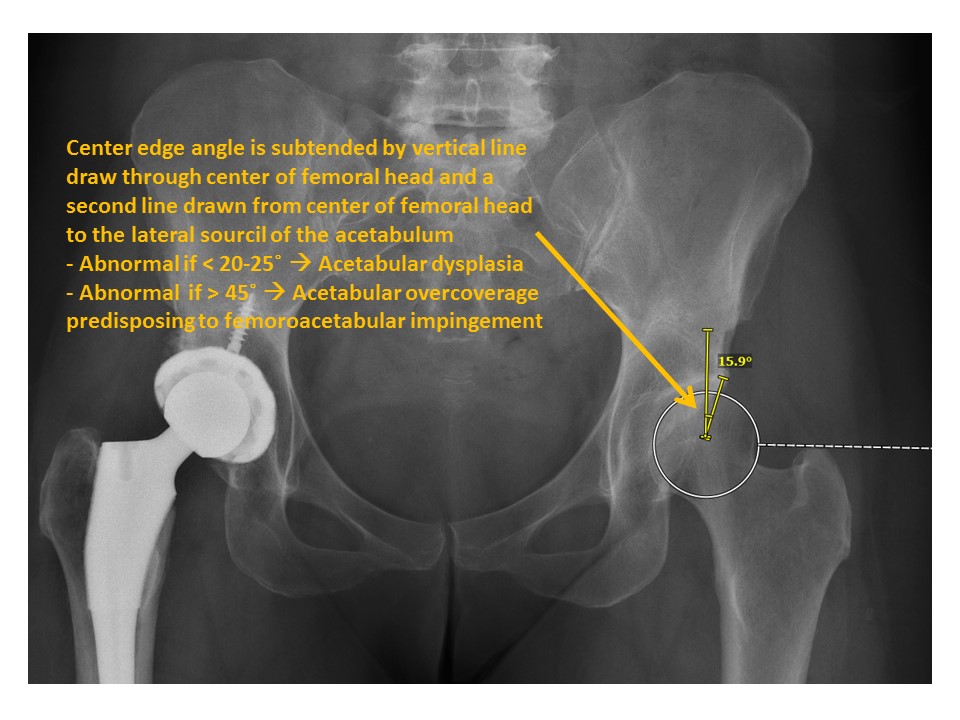

The center edge angle of the femoral heads is abnormal. [Yes/No]